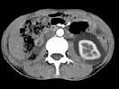

- 多项选择题女,32岁, 左腰部胀痛不适1年余,10年前因右输尿管结石、右肾重度积水行右肾切除术, CT检查如图所示,下列说法正确的是 ( )

A、平扫左肾周可见不规则的环形低密度影

B、增强扫描,肾皮质明显强化而周围的低密度影无强化

C、增强扫描肾实质期,肾实质强化而周围的低密度影无强化

D、增强扫描延迟期,肾实质强化减退而其周围则呈高密度影,对比明显

E、考虑为左侧尿外渗